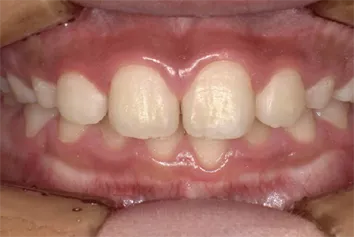

歯に穴があいている

写真3 穴があいている(黄色の破線の円))

写真3は、たとえ歯に穴があっても、非修復治療によって、むし歯をコントロールしています。穴を歯科用材料で詰めるとなると、健康な歯の部分も余分に削らないと、詰めたものがすぐに外れます。